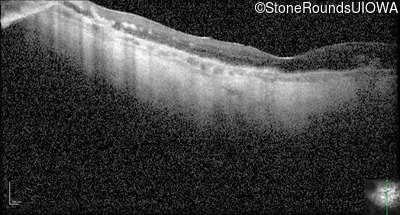

Optical Coherence Tomography - Right - Light Perception

Exemplar